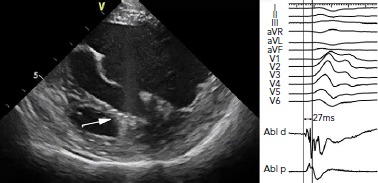

Figure 2: Morphology of the Anterior Right Ventricular Papillary Muscle as Shown by Intracardiac Echocardiography.

Note that the moderator band is connected to the base of the papillary muscle. The right panel shows ECG morphology of the ectopic beat that was successfully ablated on the tip of the anterior right ventricular papillary muscle.

Ventricular arrhythmias from the RV PM are much less frequent than arrhythmias from the LV. In general, such arrhythmias have a left bundle branch block morphology and an rS or QS pattern in lead V1 (Figure 2). Among them, the focus in the septal PM may resemble the source in the RV outflow tract on ECG, especially when the focus is on the conus PM.[11] Then, the QRS is positive from lead I to III. Some additional characteristics may favour an origin from the parahisian area,[15] including prominent R waves in leads I and aVL, and a lower R wave amplitude in lead III than lead II. Other right-sided PM arrhythmias have a wider QRS complex with a notched appearance in the precordial leads. Posterior or anterior RV papillary muscles usually have a superior axis with a late R wave transition (>V4) as compared with septal PM arrhythmias, which often have an inferior axis and an earlier R wave transition.[3,16]

As aforementioned, catheter ablation of PM arrhythmias is typically performed at the site of the earliest endocardial activation identified by activation mapping. For this purpose, a multielectrode mapping catheter could be used in an attempt to achieve faster and more precise delineation of the site of origin of arrhythmia. Sites with activation preceding approximately −25 to −30 ms the QRS complex during ectopy suggest a close proximity to the arrhythmia focus (Figure 3). In some cases, a high-frequency Purkinje potential may be present at the successful ablation site. Pace mapping could be necessary when PVCs are infrequent. However, its utility is limited due to frequent catheter instability, and also due to the fact that it identifies only the exit site and not necessarily the source.